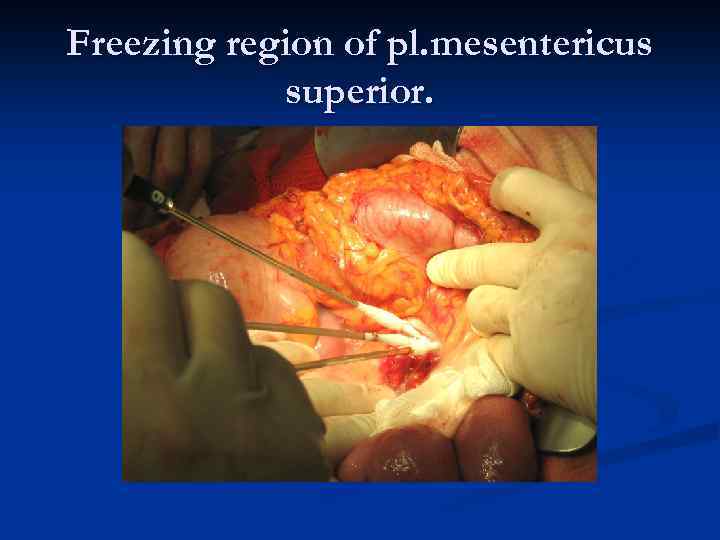

Freezing region of pl. mesentericus superior.

Freezing region of pl. mesentericus superior.

Acute ischemia of the intestine due to complete freezing of the mesenterial blood vessels Recovery of the intestine after the passive thawing of the arteries

Acute ischemia of the intestine due to complete freezing of the mesenterial blood vessels Recovery of the intestine after the passive thawing of the arteries